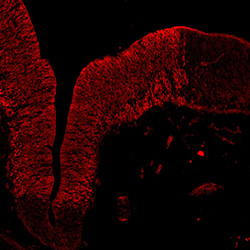

TH

13PCW human midbrain